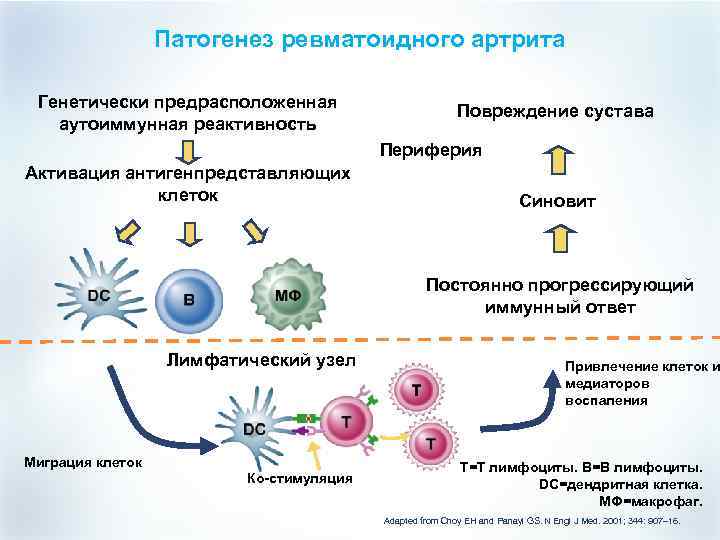

Патогенез ревматоидного артрита Генетически предрасположенная аутоиммунная реактивность Повреждение сустава Периферия Активация антигенпредставляющих клеток Синовит Постоянно прогрессирующий иммунный ответ Лимфатический узел Миграция клеток Ко-стимуляция Привлечение клеток и медиаторов воспаления T=T лимфоциты. B=B лимфоциты. DC=дендритная клетка. MΦ=макрофаг. Adapted from Choy EH and Panayi GS. N Engl J Med. 2001; 344: 907– 16.

Патогенез ревматоидного артрита Генетически предрасположенная аутоиммунная реактивность Повреждение сустава Периферия Активация антигенпредставляющих клеток Синовит Постоянно прогрессирующий иммунный ответ Лимфатический узел Миграция клеток Ко-стимуляция Привлечение клеток и медиаторов воспаления T=T лимфоциты. B=B лимфоциты. DC=дендритная клетка. MΦ=макрофаг. Adapted from Choy EH and Panayi GS. N Engl J Med. 2001; 344: 907– 16.